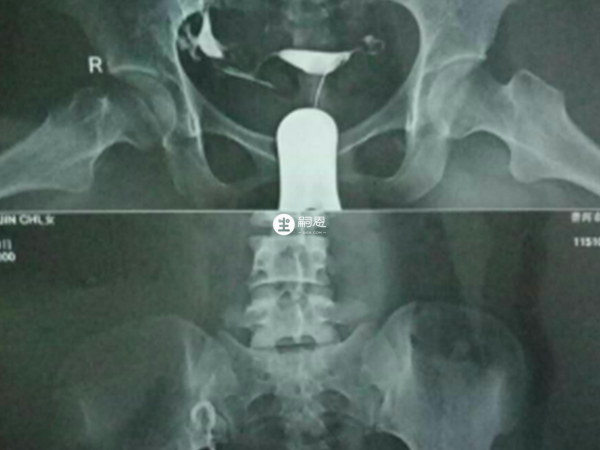

一般來說,做完造影后需要等待1-2個月,才可以進行輸卵管疏通手術。造影是一種檢查輸卵管通暢情況的方法,通過注入造影劑,可以觀察造影劑在輸卵管內的流動情況。輸卵管造影檢查後需要根據患者恢復情況再來決定合適的時間來做宮腔鏡下通水術,一般是在下個月經週期就可以做,就是在月經乾淨後,複查白帶正常,無盆腔感染的情況下做通水術就比較好。輸卵管造影檢查分為碘油造影和超聲造影,都需要使用到造影劑,很多患者做完造影后身體會不舒服,所以需要根據恢復時間來決定做通水手術的時間。

輸卵管造影檢查是不孕症的檢查專案之一,主要檢查輸卵管是否通暢,造影不能確診,只是參考,宮腹腔鏡檢查才能確診。一般是建議做宮腹腔鏡檢查術,檢查了再根據情況進行通水處理。當做完造影后多久可以做通水術,情況如下: